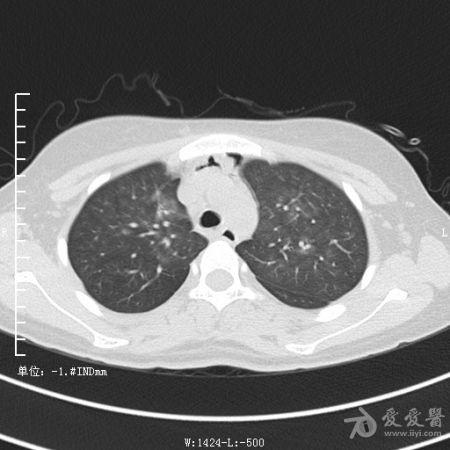

典型支气管扩张及肺水肿CT片

典型支气管扩张肺水肿